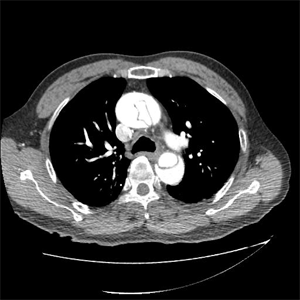

하이브리드 대동맥 수술

술전 CT (대동맥궁 대동맥류) 대동맥내 스텐트 삽입 및 머리혈관 우회술

술전 CT

머리혈관 우회술

술 후 가슴사진 및 술 후 CT

술 후 가슴사진

술 후 CT